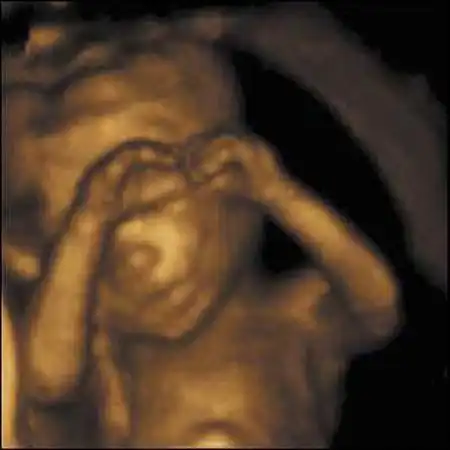

Но главное не это. Главное то, что доктор Кэмпбелл доказал, что "настоящим человеком" эмбрион становится уже в 10-11 недель...

Книга профессора потрясла ученых. В частности, в ней ученый утверждает, что ребенок шевелится уже в 12 недель, задолго до того, как мать начинает ощущать его движения...

На 11-й неделе продолжается окостенение скелета. Развиваются эндокринные железы и лимфоузлы. Сердце бьется с частотой 130-150 ударов в минуту. 9-сантиметровый ребенок двигает головой, руками, ногами, сжимает кулачки, поворачивает голову и даже пробует сосать свой палец.